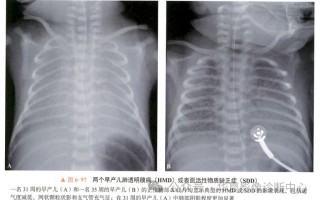

新生儿肺透明膜病的X线影像有哪些典型表现及诊断要点?